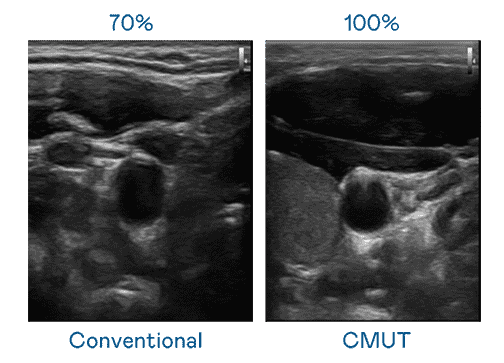

CMUT 技术是一种用电容式微机电元件来产生超音波讯号的技术。。与传统 PZT 压电式技术相比,,,,CMUT 频宽增加 30%,,,更宽频的超音波讯号让影像解析度大幅提升,,是实现高影像品质医疗超音波扫描、、、促进精准医疗发展的关键技术。。

超音波影像的解析度高低,,,首先取决于探头能发出的讯号频宽。。www.z6.com CMUT 可提供高清晰的超音波讯号,,提供高频宽、、、高灵敏度、、、影像纹理细节更高的超音波影像,,协助医护人员缩短影像判读时间及利用精准的医疗影像进行诊断。。